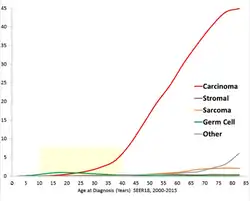

The risk of ovarian cancer increases with age. Most cases of ovarian cancer develop after menopause.[16] It is also more common in women who have ovulated more over their lifetime.[17] This includes those who have never had children, those who began ovulation at a younger age and those who reach menopause at an older age.[5] Other risk factors include hormone therapy after menopause, fertility medication, and obesity.[4][6] Factors that decrease risk include hormonal birth control, tubal ligation, pregnancy, and breast feeding.[6] About 10% of cases are related to inherited genetic risk; women with mutations in the genes BRCA1 or BRCA2 have about a 50% chance of developing the disease.[5] Some family cancer syndromes such as hereditary nonpolyposis colon cancer and Peutz-Jeghers syndrome also increase the risk of developing ovarian cancer.[16] Epithelial ovarian carcinoma is the most common type of ovarian cancer, comprising more than 95% of cases.[5] There are five main subtypes of ovarian carcinoma, of which high-grade serous carcinoma (HGSC) is the most common.[5] Less common types of ovarian cancer include germ cell tumors[18] and sex cord stromal tumors.[5] A diagnosis of ovarian cancer is confirmed through a biopsy of tissue, usually removed during surgery.[1]

Ovarian cancers are classified according to the microscopic appearance of their structures (histology or histopathology). Histology dictates many aspects of clinical treatment, management, and prognosis. The gross pathology of ovarian cancers is very similar regardless of histologic type: ovarian tumors have solid and cystic masses.[29] According to SEER, the types of ovarian cancers in women age 20 and over are:[66]

Ovarian cancers are histologically and genetically divided into type I or type II. Type I cancers are of low histological grade and include endometrioid, mucinous, and clear-cell carcinomas. Type II cancers are of higher histological grade and include serous carcinoma and carcinosarcoma.[28]

Sex cord-stromal tumor

Germ cell tumor

Germ cell tumors of the ovary develop from the ovarian germ cells.[70] Germ cell tumor accounts for about 30% of ovarian tumors, but only 5% of ovarian cancers, because most germ-cell tumors are teratomas and most teratomas are benign. Malignant teratomas tend to occur in older women, when one of the germ layers in the tumor develops into a squamous cell carcinoma.[26] Germ-cell tumors tend to occur in young women (20s–30s) and girls, making up 70% of the ovarian cancer seen in that age group.[33] Germ-cell tumors can include dysgerminomas, teratomas, yolk sac tumors/endodermal sinus tumors, and choriocarcinomas, when they arise in the ovary. Some germ-cell tumors have an isochromosome 12, where one arm of chromosome 12 is deleted and replaced with a duplicate of the other.[26] Most germ-cell cancers have a better prognosis than other subtypes and are more sensitive to chemotherapy. They are more likely to be stage I at diagnosis.[32] Overall, they metastasize more frequently than epithelial ovarian cancers. In addition, the cancer markers used vary with tumor type: choriocarcinomas are monitored with beta-HCG and endodermal sinus tumors with alpha-fetoprotein.[26]